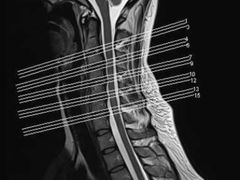

• 上海中医药大学附属曙光医院(东部)

• -上海中医药大学附属曙光医院(东部)